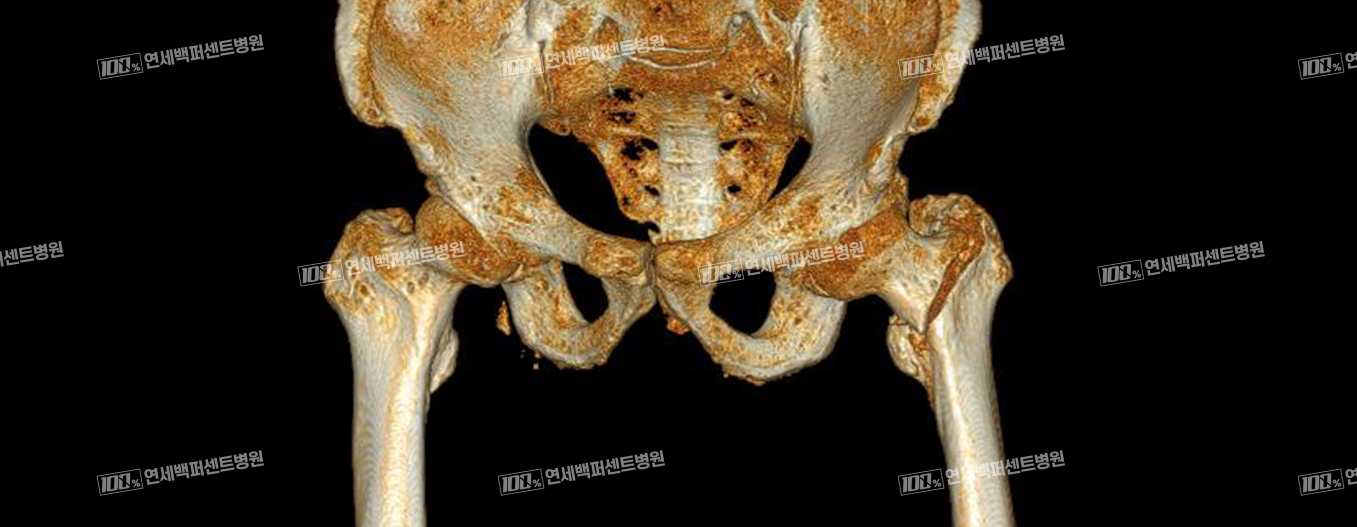

고관절 골절

대퇴경부 골절 X-ray

전자간 골절 X-ray